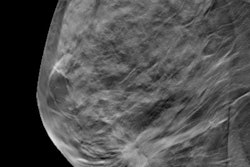

Women who undergo additional testing for a noncancerous lesion following their initial screening mammography exam are increasingly more likely to develop cancer depending on the type of premalignant lesion identified, according to an article published online on 17 June in Cancer.

The researchers found that individuals who were recalled for follow-up imaging -- with mammography, ultrasound, or MRI -- after their initial screening exam had a statistically significant increase in breast cancer risk, compared with those who were not recalled. The trend also applied to individuals who were recalled for additional testing for a benign lesion, hyperplasia with atypia, and carcinoma in situ.

Specifically, the incidence rate of breast cancer for these recalled individuals increased by approximately twofold for those who had a negative follow-up imaging exam or a benign biopsy, threefold for those with atypia, and fourfold for those with carcinoma in situ.